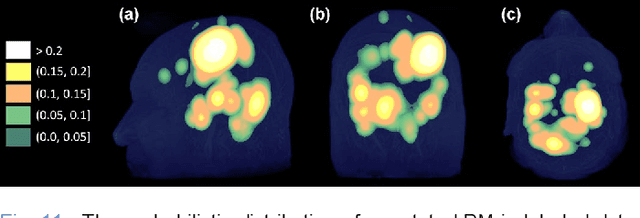

Abstract:The detection of brain metastases (BM) in their early stages could have a positive impact on the outcome of cancer patients. We previously developed a framework for detecting small BM (with diameters of less than 15mm) in T1-weighted Contrast-Enhanced 3D Magnetic Resonance images (T1c) to assist medical experts in this time-sensitive and high-stakes task. The framework utilizes a dedicated convolutional neural network (CNN) trained using labeled T1c data, where the ground truth BM segmentations were provided by a radiologist. This study aims to advance the framework with a noisy student-based self-training strategy to make use of a large corpus of unlabeled T1c data (i.e., data without BM segmentations or detections). Accordingly, the work (1) describes the student and teacher CNN architectures, (2) presents data and model noising mechanisms, and (3) introduces a novel pseudo-labeling strategy factoring in the learned BM detection sensitivity of the framework. Finally, it describes a semi-supervised learning strategy utilizing these components. We performed the validation using 217 labeled and 1247 unlabeled T1c exams via 2-fold cross-validation. The framework utilizing only the labeled exams produced 9.23 false positives for 90% BM detection sensitivity; whereas, the framework using the introduced learning strategy led to ~9% reduction in false detections (i.e., 8.44) for the same sensitivity level. Furthermore, while experiments utilizing 75% and 50% of the labeled datasets resulted in algorithm performance degradation (12.19 and 13.89 false positives respectively), the impact was less pronounced with the noisy student-based training strategy (10.79 and 12.37 false positives respectively).

Abstract:Early detection of brain metastases (BM) is one of the determining factors for the successful treatment of patients with cancer; however, the accurate detection of small BM lesions (< 15mm) remains a challenging task. We previously described a framework for the detection of small BM in single-sequence gadolinium-enhanced T1-weighted 3D MRI datasets. It combined classical image processing (IP) with a dedicated convolutional neural network, taking approximately 30 seconds to process each dataset due to computation-intensive IP stages. To overcome the speed limitation, this study aims to reformulate the framework via an augmented pair of CNNs (eliminating the IP) to reduce the processing times while preserving the BM detection performance. Our previous implementation of the BM detection algorithm utilized Laplacian of Gaussians (LoG) for the candidate selection portion of the solution. In this study, we introduce a novel BM candidate detection CNN (cdCNN) to replace this classical IP stage. The network is formulated to have (1) a similar receptive field as the LoG method, and (2) a bias for the detection of BM lesion loci. The proposed CNN is later augmented with a classification CNN to perform the BM detection task. The cdCNN achieved 97.4% BM detection sensitivity when producing 60K candidates per 3D MRI dataset, while the LoG achieved 96.5% detection sensitivity with 73K candidates. The augmented BM detection framework generated on average 9.20 false-positive BM detections per patient for 90% sensitivity, which is comparable with our previous results. However, it processes each 3D data in 1.9 seconds, presenting a 93.5% reduction in the computation time.